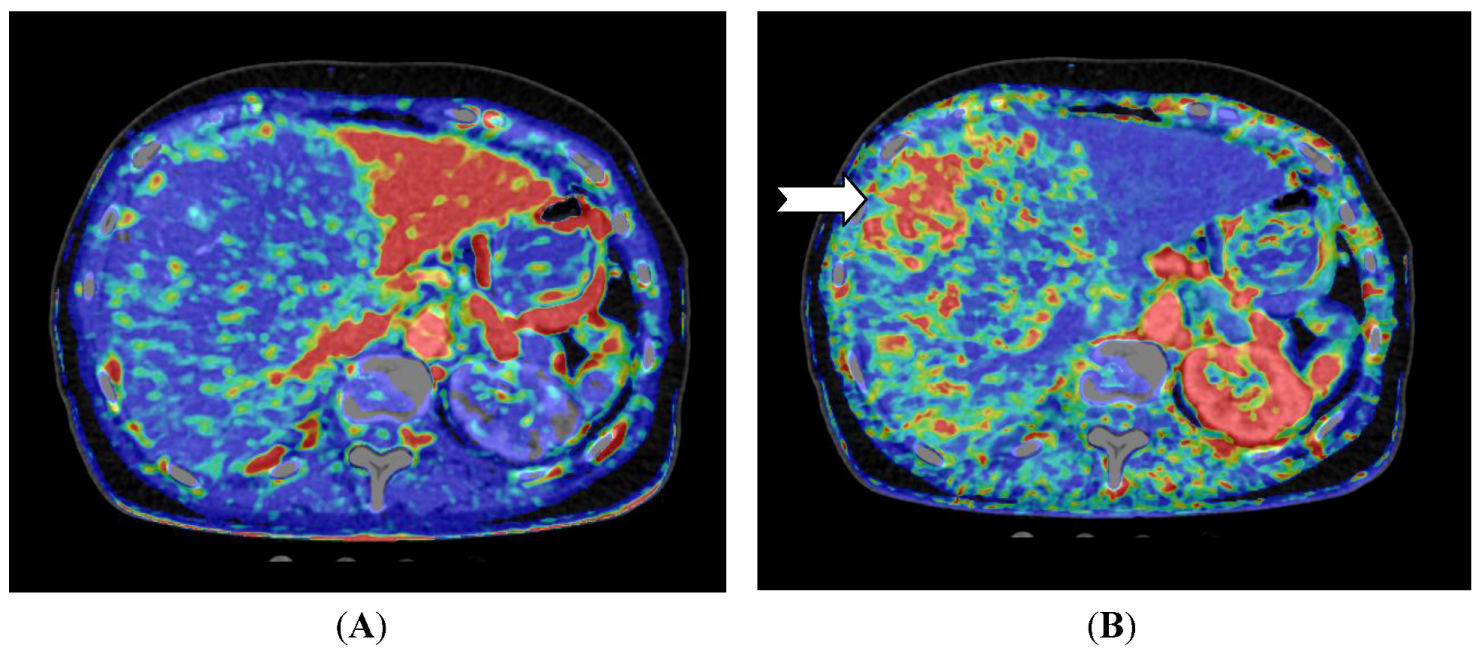

Figure 3.

CT perfusion examination of a 77-year-old female after right-sided portal vein embolization prior to liver resection. The patient has a large HCC in the right liver lobe and segment 4. (A) Perfusion shows the portal flow, which is eliminated on the right side and elevated in the left liver lobe; (B) Perfusion index (Arterial Flow/Arterial Flow + Portal Flow). This index is low in the left side due to elevated portal flow, and the index is high in all of the embolized segments, but highest in the vascular part of the HCC (arrow) (Images reconstructed with Vitrea 6.2, Vital Images A Toshiba Medical Systems Group).